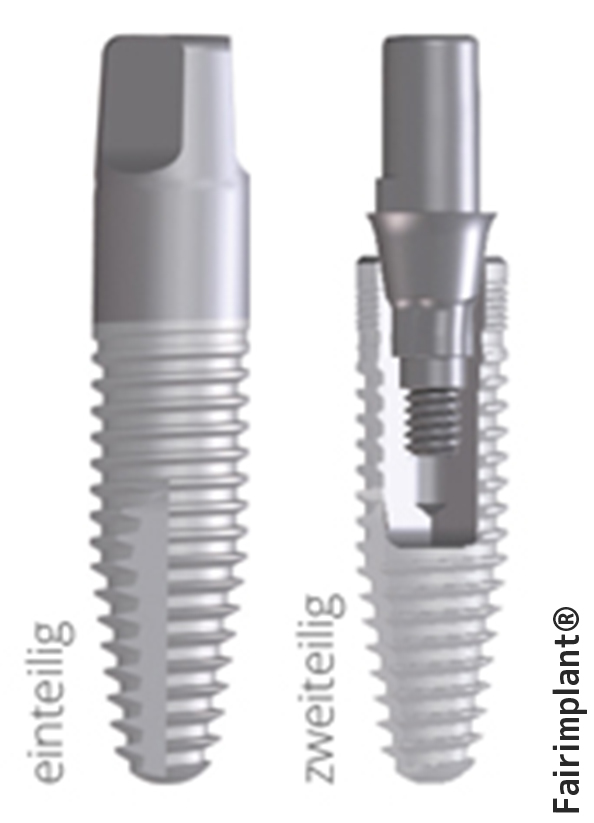

Implantate sind eine solide Basis für hochwertigen Zahnersatz. Wie eine künstliche Zahnwurzel werden die Titanschrauben im Kieferknochen verankert und dann durch den passenden Zahnersatz ergänzt. Von einzelnen Kronen in einer Zahnlücke über Brücken beim Ersatz mehrerer Zähne bis hin zur Komplettsanierung ist alles möglich. Gegenüber dem herkömmlichen Zahnersatz haben die gut verträglichen Titan-Implantate zahlreiche Vorteile: Implantate verwachsen mit dem Kieferknochen und sind dadurch genauso belastbar wie gesunde, natürliche Zähne. Bei herkömmlichen Brücken müssen gesunde Nachbarzähne beschliffen werden. Implantate übernehmen diese Pfeiler-Funktion und schonen so die umliegenden Zähne. Die implantierten Titanstifte fühlen sich nach einer Weile völlig natürlich an. Ein Fremdkörpergefühl wie bei Prothesen entfällt. Durch Nichtbelastung bei Zahnlücken oder ständigen Prothesendruck baut sich mit der Zeit der Kieferknochen ab und der Mund sieht eingefallen aus. Implantate erhalten den für ein jugendliches Aussehen so wichtigen Kieferknochen und tragen damit wesentlich zu einem ästhetischen Gesamteindruck bei. Implantate sind ein Segen für Träger nicht saugender Totalprothesen. Schon zwei Implantate stabilisieren Ihre Prothese so, dass Sie im Alltag ein hohes Maß an Sicherheit gewinnen. Zweiteilige und einteilige Implantate Einteilige Implantate bestehen aus nur einer Komponente. Der für den Zahnersatz nötige Aufbau ist dabei in die Implantatschraube integriert. Nach dem Einbringen ragt der Implantataufbau, beispielsweise ein Pfosten für eine aufzusetzende Krone, schon nach dem ersten Eingriff aus dem Zahnfleisch heraus. Eine Freilegungsoperation ist hier nicht erforderlich. Stimmen die knöchernen Voraussetzungen können in der Regel einteilige Implantate mit der minimalinvasiven Methode der Implantation eingesetzt werden, wobei nur ein kleiner operativer Eingriff unter maximaler Schonung benachbarter Bereiche vorgenommen wird. Aufgrund der schnellen minimalinvasiven Behandlung, den einfacheren Behandlungsabläufen, sowie der geringeren Kosten sind einteilige Implantate eine attraktive Variante zu den herkömmlichen zweiteiligen Implantatsystemen. Wir beraten Sie gerne, ob und welche Art der Implantate bei Ihnen ratsam sind und wie eine Versorgung genau aussehen kann. Dr. Jürgen Wenzel ist zertifizierter Implantologe und Mitglied der Deutschen Gesellschaft für Implantologie und damit Ihr kompetenter Ansprechpartner auf diesem Gebiet.

Zweiteilige Implantate bestehen aus mehreren Komponenten und haben den Vorteil, dass sie zunächst ohne Beeinträchtigung geschützt unter der Schleimhaut einheilen können und mit individuellen Aufbauten den prothetischen Erfordernissen angepasst werden können. Allerdings ist hierzu ein zweiter Eingriff erforderlich, bei der mit speziellen Aufbauten ein Durchtrittsprofil durch die Schleimhaut geschaffen werden muss.

Zweiteilige Implantate bestehen aus mehreren Komponenten und haben den Vorteil, dass sie zunächst ohne Beeinträchtigung geschützt unter der Schleimhaut einheilen können und mit individuellen Aufbauten den prothetischen Erfordernissen angepasst werden können. Allerdings ist hierzu ein zweiter Eingriff erforderlich, bei der mit speziellen Aufbauten ein Durchtrittsprofil durch die Schleimhaut geschaffen werden muss.